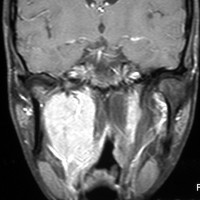

遺伝歴があり30代くらいです。黄色の矢印で示す右側はglomus vagale,左側は上がglomus jugulare、左下がglomus caroticumです。教科書に載せたいくらい典型的な部位に発生しています。無症状ですからもちろん治療はしません。6年くらい経過観察していますがほとんど増大もしません。